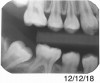

A 28-year-old woman, who previously had braces, had circumferential gumline decalcification (Figure 1) and wished to arrest lesions before they worsened (bitewing, Figure 2). The following protocol is consistent with the product instructions for the resin infiltration material from DMG America, which is the only commercially available resin infiltration system in the US.

Fig 2.  Circumferential gumline decalcification (Fig 1) and bitewing (Fig 2) of a 28-year-old woman.

Figure 2